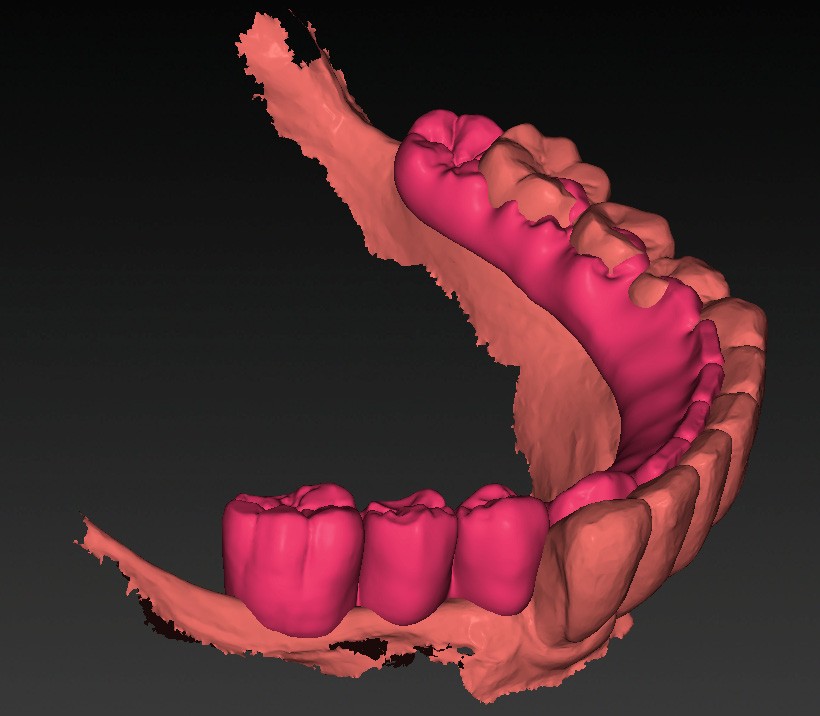

- les empreintes (fig. 3) transmises au laboratoire pour la réalisation d’un wax-up digital (fig. 4) préfigurant la position idéale des dents prothétiques. Ce modèle prothétique virtuel permet de déterminer la position, l’axe et la profondeur idéale des implants en fonction du couloir osseux, des tissus mous et du positionnement souhaité des puits de vissage.

La patiente présente une classe III squelettique marquée. Le projet prothétique prévoit un repositionnement en bout à bout des dents et un décalage mésio-distal d’environ ½ dent pour garantir une esthétique satisfaisante…